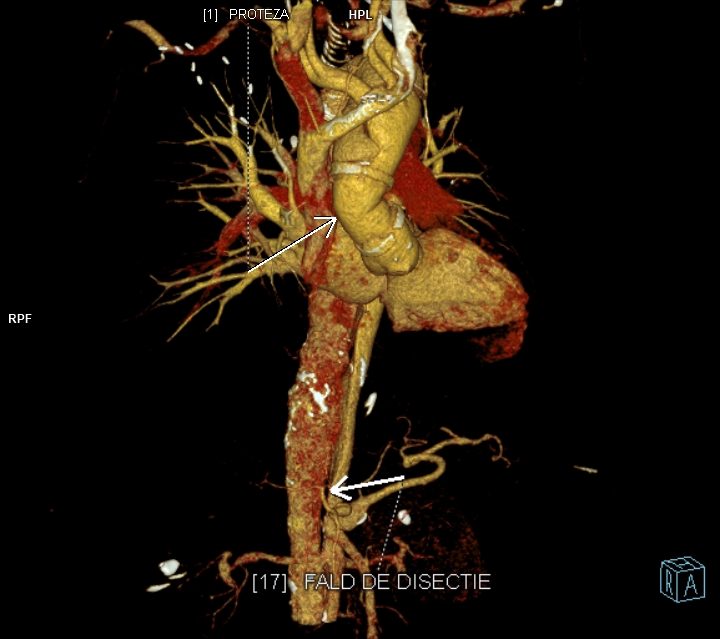

Figura 4: reconstrucție VRT din angioCT arterial

Discuţie caz nr 126: Investigația CT a fost realizată pentru control postoperator la un pacient cu proteză de aorta ascendentă pentru disecție de aorta Stanford tip A operată. Se evidențiază proteză de aortă ascendentă în poziție normală, fără dezvoltări anevrismale la nivelul anastomozelor precum și disecție de aorta toracică și abdominală restantă cu orificii de intrare proximal precum și distal în vecinătatea originii arterei renale drepte, iar faldul de disecție nu evoluează la nivelul ramurilor. În plus, se evidențiază stenoză proximală de trunchi celiac cu dilatație poststenotică